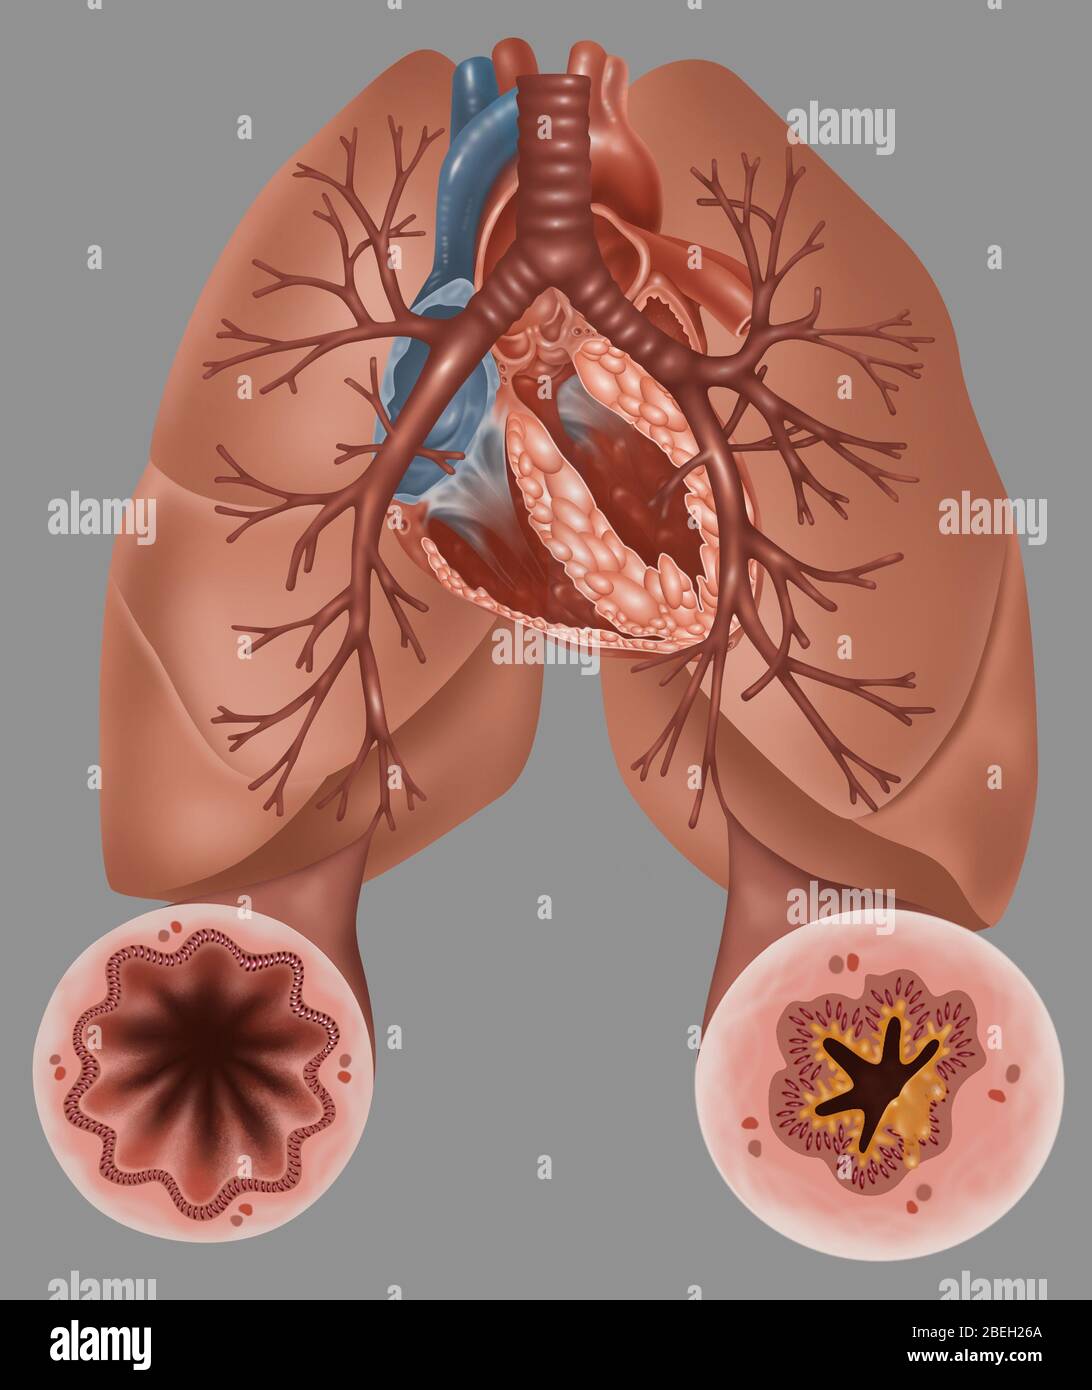

Lungs - Bronchial Mucus. Shown is bronchial airway obstruction and narrowing due to viscid mucus. Stock Photohttps://www.alamy.com/image-license-details/?v=1https://www.alamy.com/stock-photo-lungs-bronchial-mucus-shown-is-bronchial-airway-obstruction-and-narrowing-130806404.html

Lungs - Bronchial Mucus. Shown is bronchial airway obstruction and narrowing due to viscid mucus. Stock Photohttps://www.alamy.com/image-license-details/?v=1https://www.alamy.com/stock-photo-lungs-bronchial-mucus-shown-is-bronchial-airway-obstruction-and-narrowing-130806404.htmlRFHGPMW8–Lungs - Bronchial Mucus. Shown is bronchial airway obstruction and narrowing due to viscid mucus.

Asthma Pathology Stock Photohttps://www.alamy.com/image-license-details/?v=1https://www.alamy.com/asthma-pathology-image353187474.html

Asthma Pathology Stock Photohttps://www.alamy.com/image-license-details/?v=1https://www.alamy.com/asthma-pathology-image353187474.htmlRF2BEH26A–Asthma Pathology